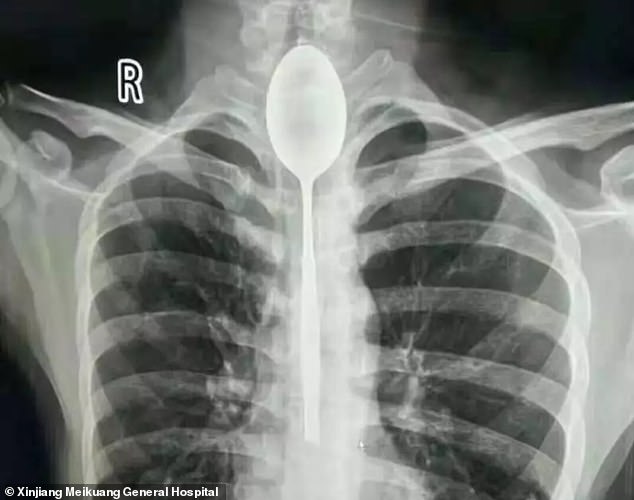

Мужчина жил с металлической ложкой, застрявшей в пищеводе, в течение целого года

Год назад этот мужчина проглотил 8-дюймовую металлическую ложку, пытаясь продемонстрировать глупый фокус. Столовый прибор застрял в пищеводе, но, видя, что он нормально может есть и пить, горе-фокусник не обращался за медицинской помощью. Мужчина утверждает, что лишь несколько дней назад он начинал испытывать боли в груди.

Пострадавший, пожелавший остаться анонимным, рассказал врачам, что проглотил ложку из нержавеющей стали во время пьяного спора. Он сказал своим друзьям, что может проглотить данный предмет, а затем сделал это, привязав к ложке веревку. Но все пошло не по плану, и кухонная утварь застряла в пищеводе мужчины. Вместо того, чтобы немедленно отправиться в больницу, он ждал пока ложка начнет мешать ему нормально есть и пить.

Ложка могла остаться в пищеводе гораздо дольше, если бы мужчина не получил удар в грудь несколько дней назад, после чего стал испытывать мучительную боль и затрудненное дыхание. Наконец он отправился в больницу, где вскользь сообщил врачам, что живет с металлической ложкой, застрявшей в пищеводе.

«Я был потрясен. У нас подобных случаев в практике не было», — написал доктор Юй Сиву в заявлении, опубликованном больницей. «Когда мы осмотрели пациента, его пищевод уже был воспален».

Обсудив лучший курс действий, врачи в больнице Синьцзяна решили, что лучший способ извлечь ложку — через рот. Пациенту дали общий наркоз, и команда врачей провела два часа, пытаясь достать 8-дюймовую ложку с помощью эндоскопического оборудования.

Больница сообщила СМИ, что мужчина идет на поправку и вскоре его выпишут.

Mail Online сообщает, что этот случай редок но, безусловно, не уникален. Например, в 2015 году врачам удалось извлечь шестидюймовую металлическую ложку у женщины, которая проглотила ее во время слишком быстрого поедания лапши.